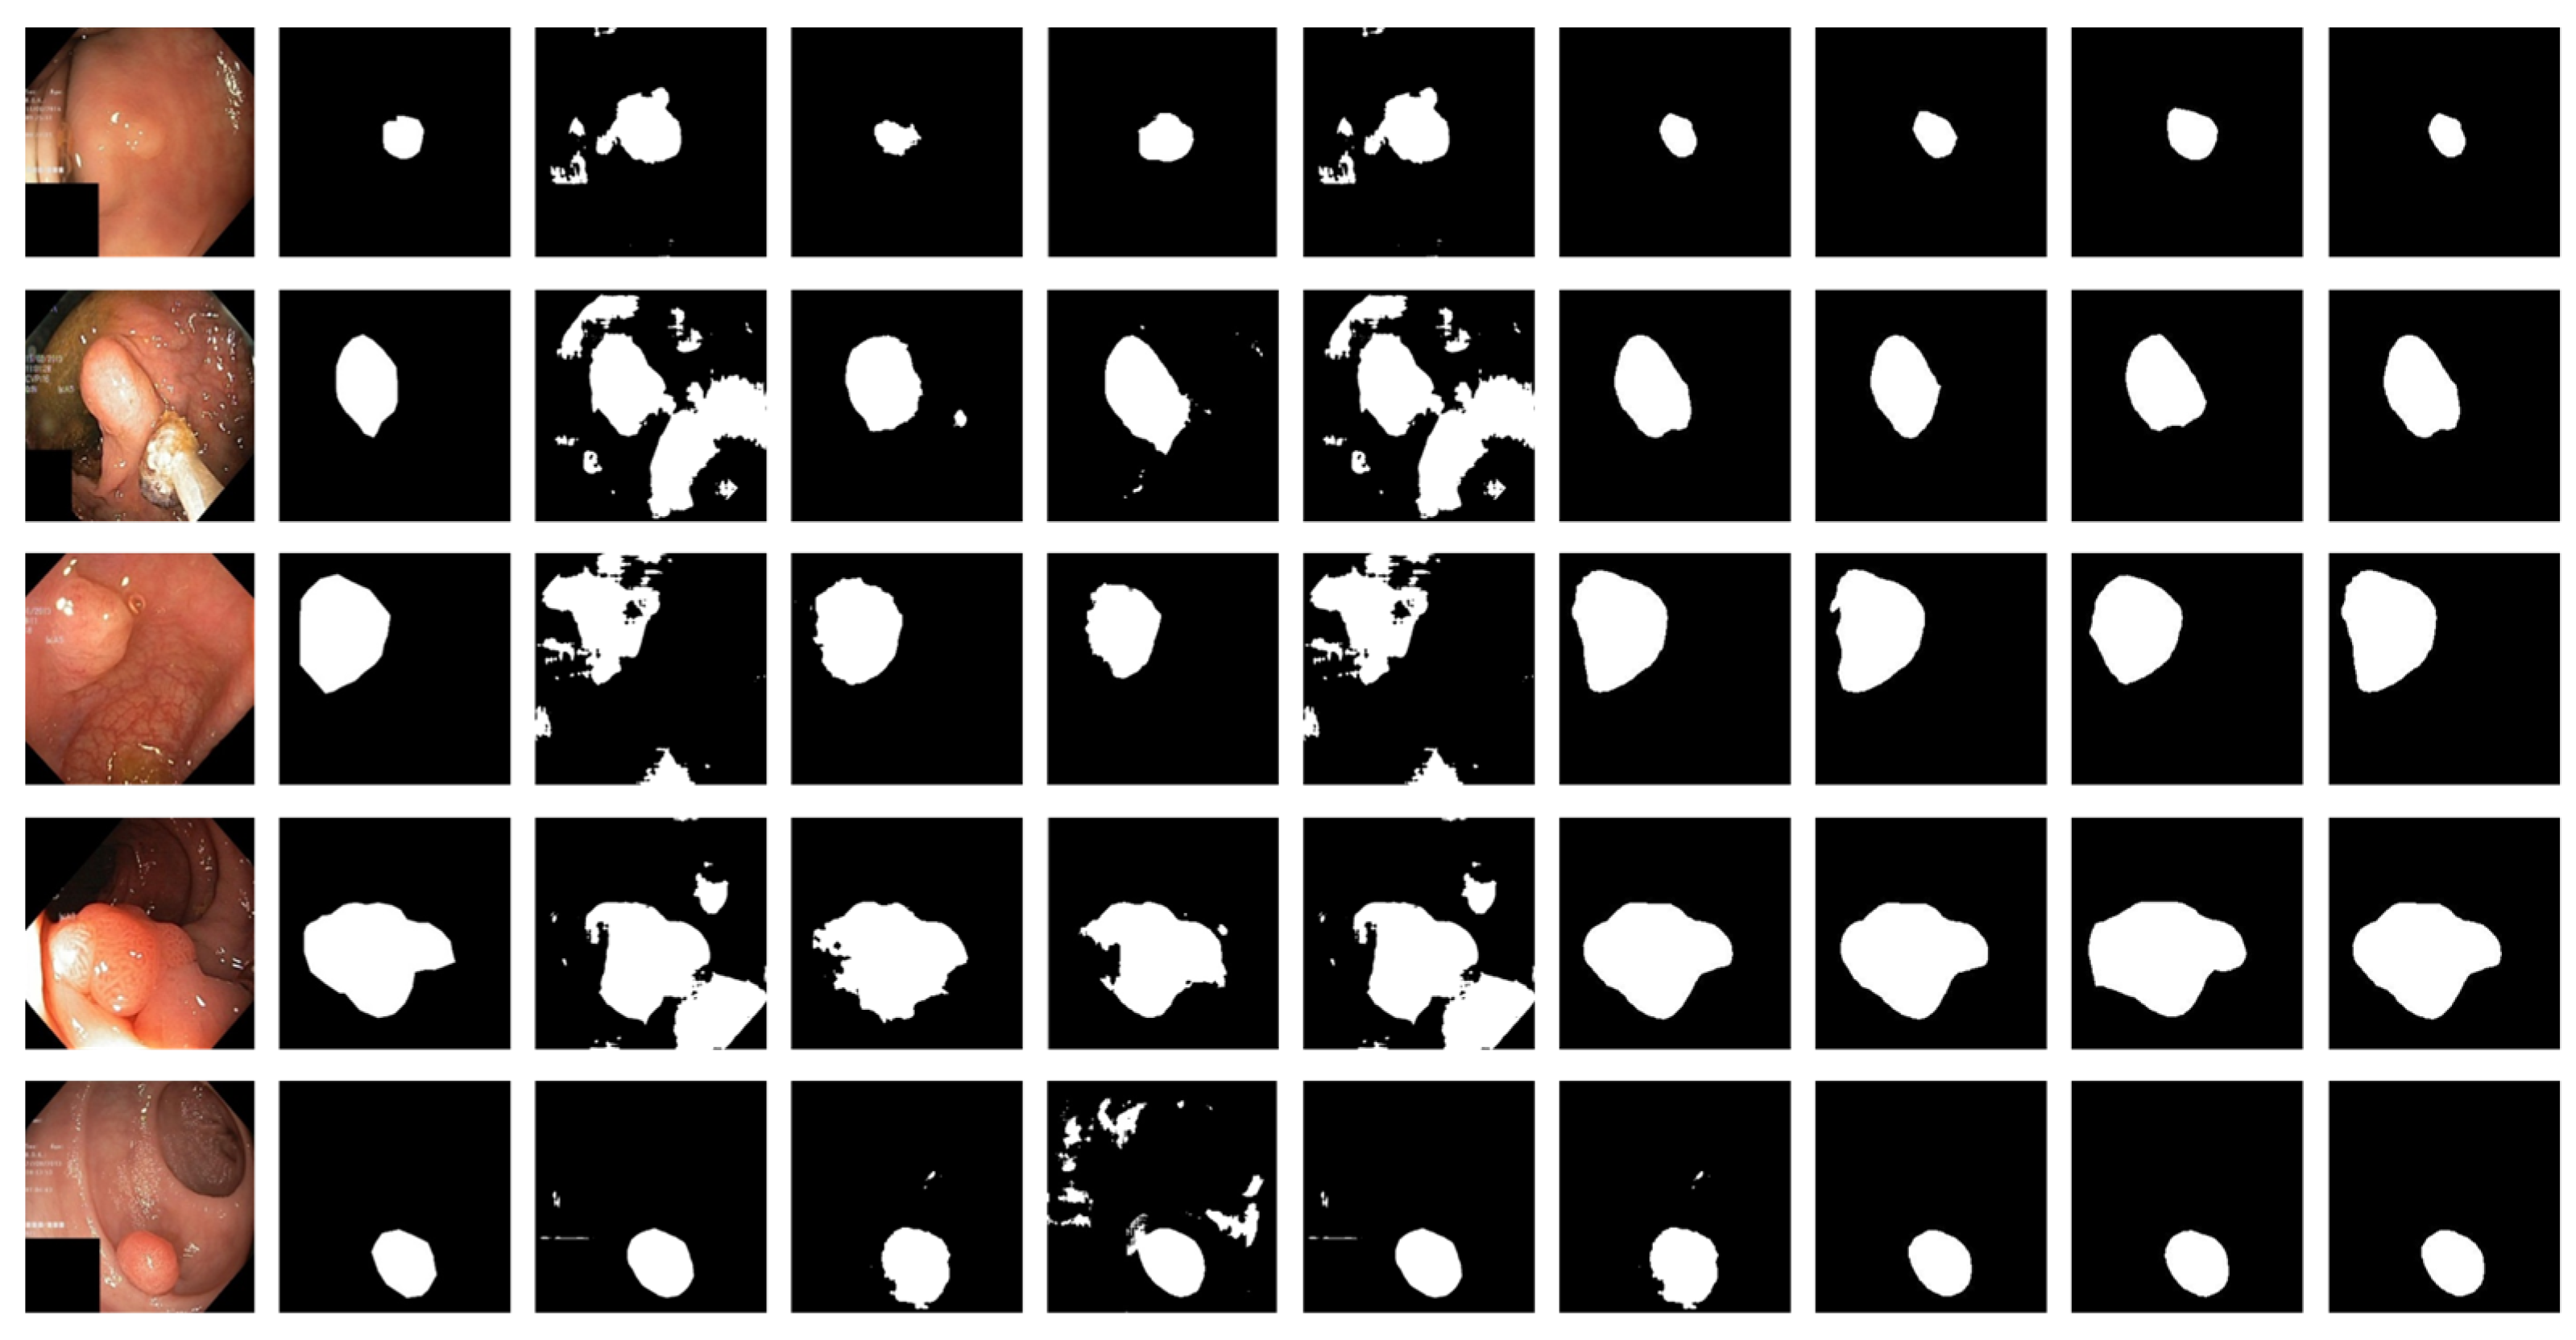

3.4. Experimental Results